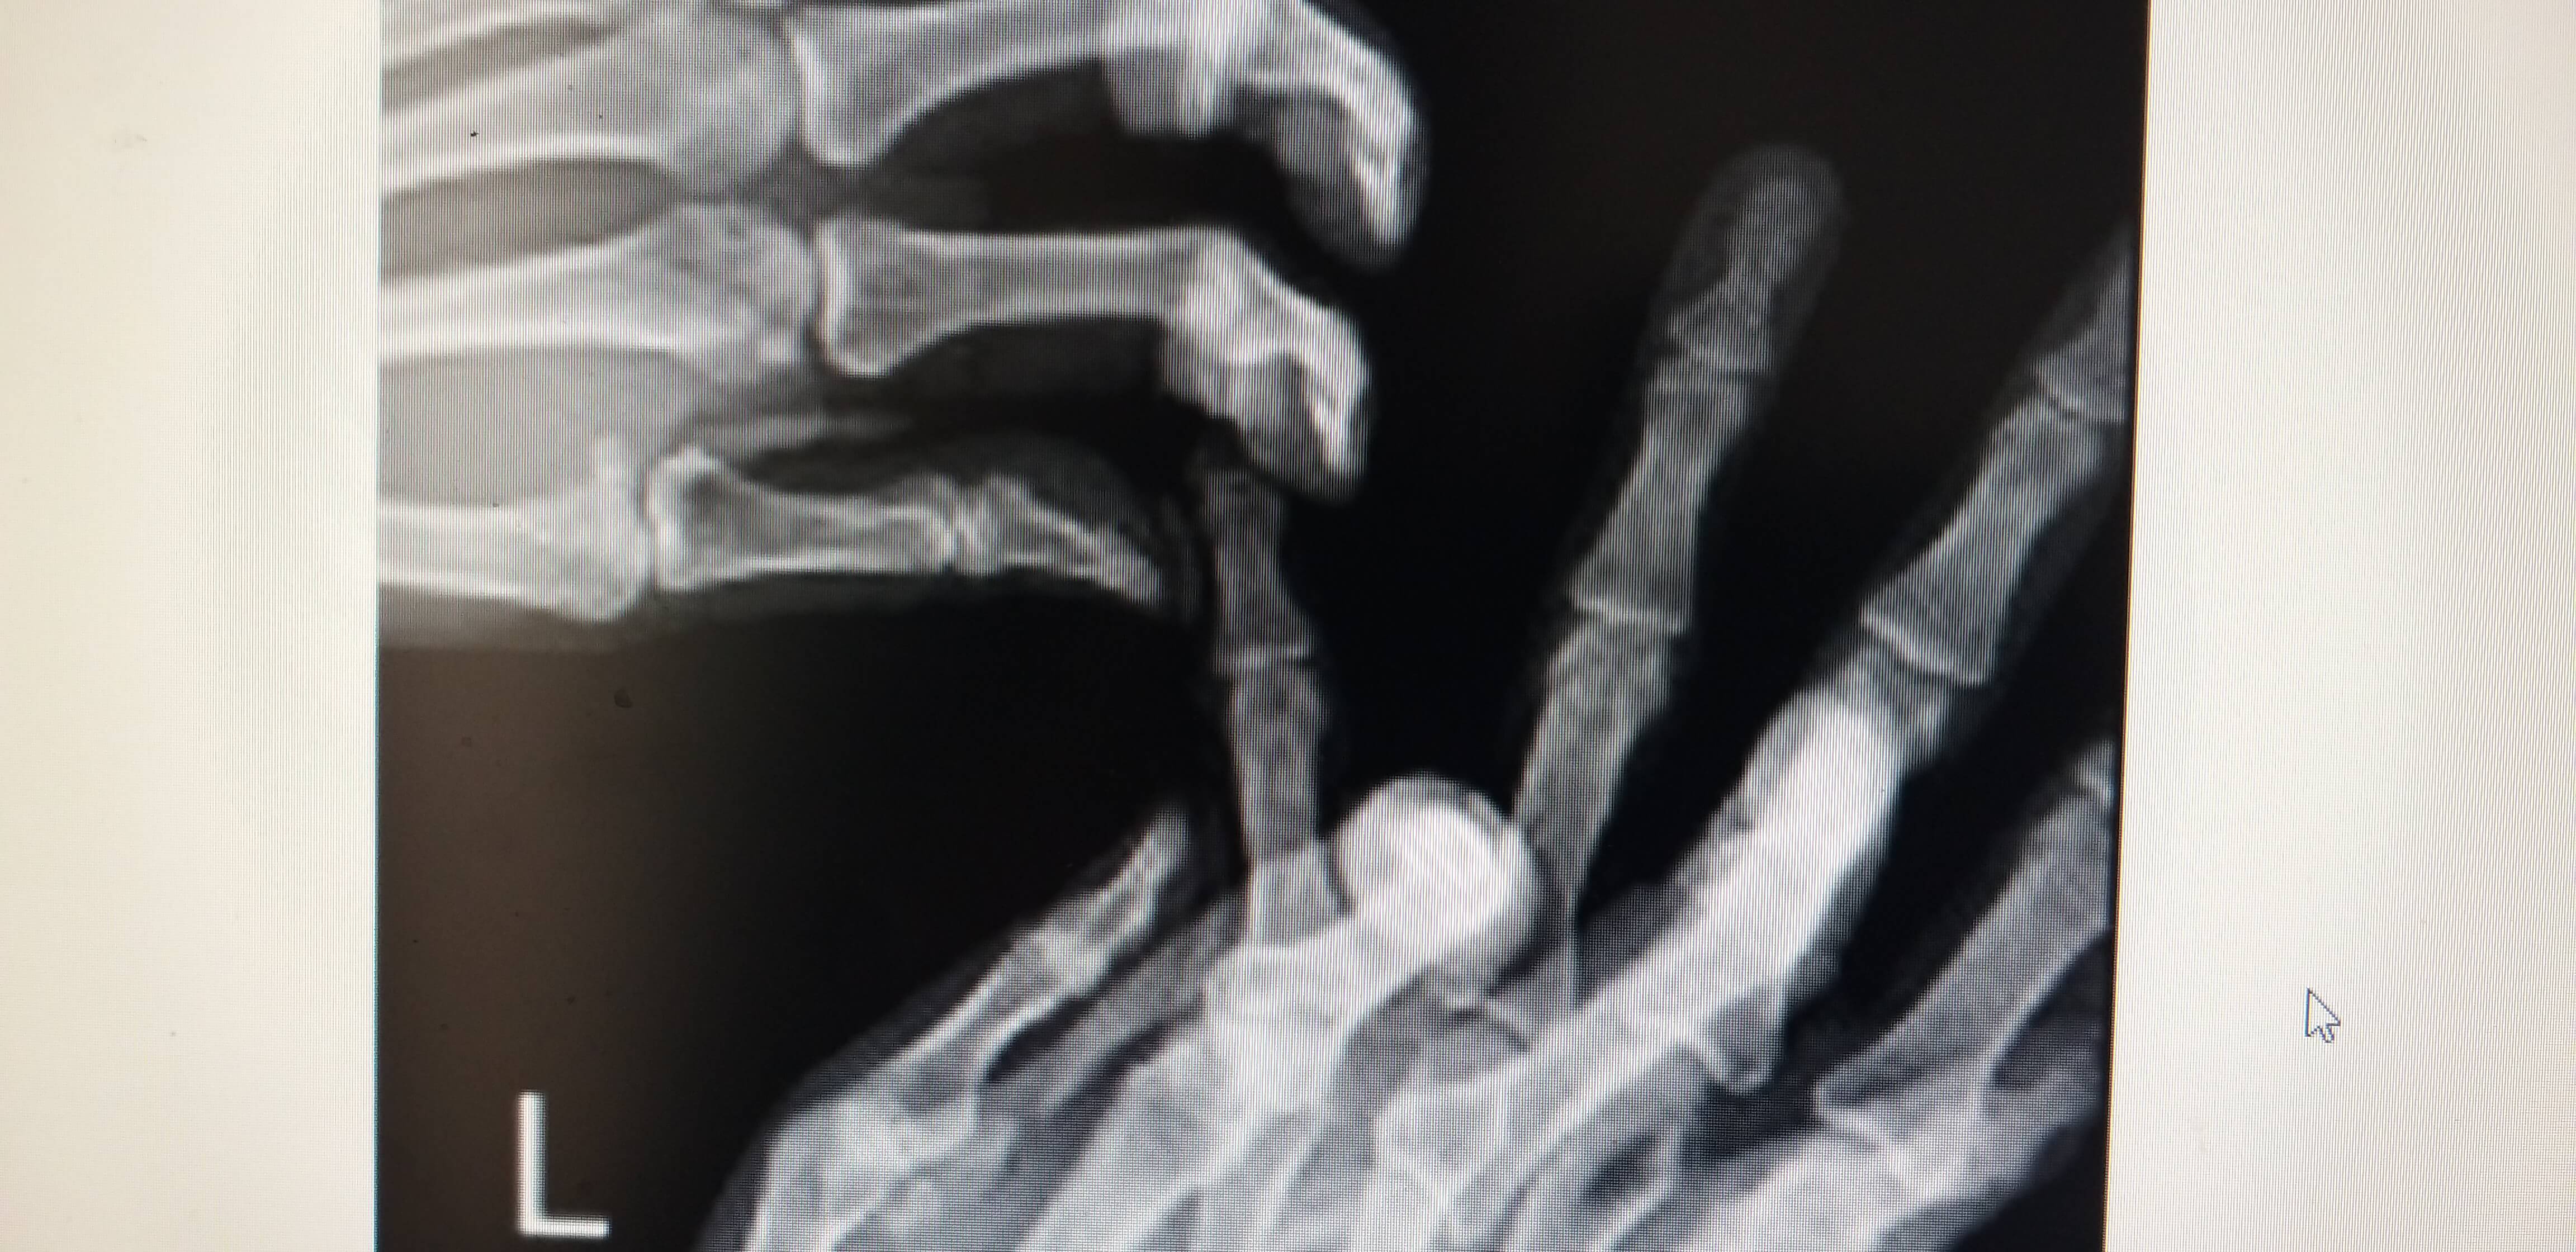

아래의 사진과 같이 새끼손가락이 옆으로 휘어져 버렸습니다.

수지전문 병원이 집근처에 있어 바로 검사를 시행하였습니다. 아래사진에서 보듯이 X-RAY 상에서 손가락이 옆으로 휘어져 있습니다.

의사선생님 말씀으로는 인대가 완전 파열된 상태이며 인대가 원래 뼈에 붙어있는 상태에서 충격이나 골절로 파열될때 뼈조각이 같이 떨어지는 경우가있다고 하셨고 나의 상태도 손가락 인대 완전 파열과 뼈조각 제거 수술을 바로 진행해야 된다는 진단을 받았습니다.

참고로 수지전문 병원마다 의사의 소견이 틀리며 처음으로 간 병원은 X-ARY 초음파 검사만 하고 바로 수술결정을 내렸습니다.